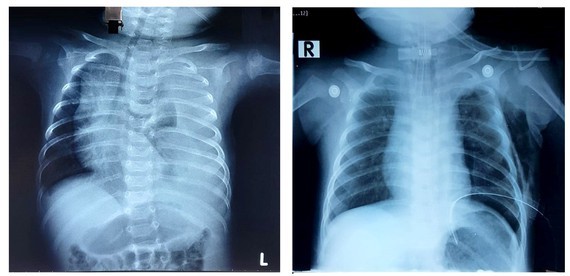

Hình ảnh chụp X-quang của bé trai sau ca phẫu thuật thành công bằng phương pháp thắt ống ngực.

Sau khi có kết quả chụp X-quang phổi của bé phát hiện tình trạng tràn dịch màng phổi bên trái lượng nhiều, gây nên tình trạng chèn ép nhu mô phổi khiến bé không thở được. Các bác sĩ đã tiến hành đặt dẫn lưu màng phổi và ghi nhận rất nhiều dịch đục như sữa chảy ra từ khoang màng phổi.

Bác sĩ Nguyễn Trần Việt Tánh, phẫu thuật viên chính của ca mổ cho biết, ekíp mổ đã quan sát lồng ngực bé bằng nội soi kỹ lưỡng, tìm và thắt được ống ngực (kích thước chỉ bằng 0,2mm) và không làm ảnh hưởng tới các cấu trúc xung quanh. Ngay sau mổ dịch dưỡng trấp màng phổi không còn ghi nhận chảy ra, bệnh nhi được rút ống dẫn lưu sau 2 ngày theo dõi. Nhờ được thực hiện bằng phẫu thuật nội soi xâm lấn tối thiểu, bệnh nhi hồi phục ăn uống lại bình thường rất nhanh và xuất viện 7 ngày sau mổ.